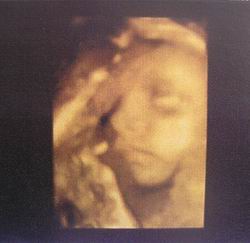

Ma voltunk 4D-sen, minden oké a KISCSAJJAL!, ami mostmár tuti (jöhetnek a rózsaszín csodák minden mennyiségben ;))

Teszek fel pár képet: olyan édi és már 1036 gramm!

Kép Kép

Az első képen nagyon tisztán látszik a pofija és naon cuki!!!

Ahogy bari is írta,hihetetlen,hogymár 1 kiló felett vannak!

Bogi nagyon szép a abád,de a kép minőség nem annyira jó

Szerintem is írtó cukor. Ásítozott, szopizta az ujját, még a nyelvecskéjét is kidugta nekünk. Az UH végére pedig elaludt. :lol: